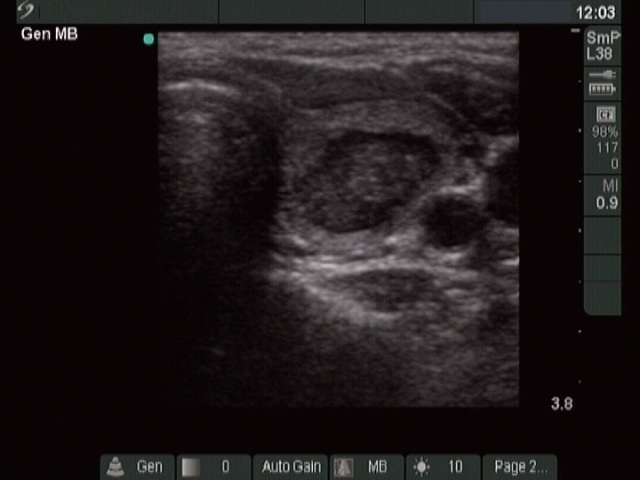

Three months after the sclerotherapy (ultrasonographic picture 1)

Left lobe, horizontal scan. The lesion shows a significant shrinkage.